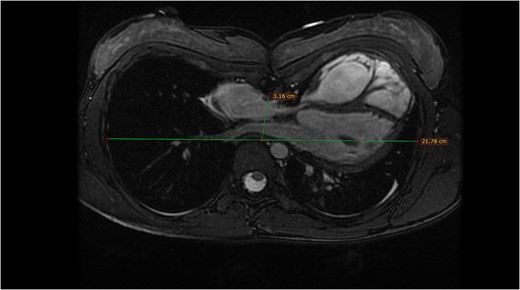

The second patient is a 13-year-old female with a past medical history of pulmonary atresia. After a failed balloon valvuloplasty, she underwent an urgent surgical pulmonary valvulotomy during early infancy, presenting additionally with pectus excavatum in childhood. Presently, she has been referred to our heart center due to the diagnosis of severe pulmonary valve regurgitation. The findings were corroborated through echocardiography and MRI tomography (Fig. 2) with a regurgitant fraction of 37%, RVEF 51%, and moderate pectus excavatum, with a Haller index of 3.2.